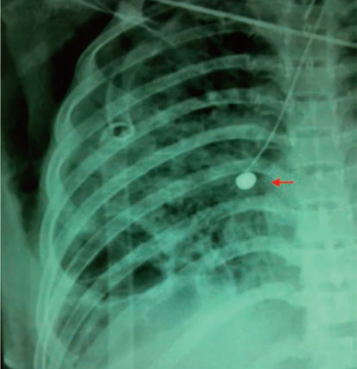

患者,男性,70岁,食管鳞癌侵犯左主支气管,Ⅰ型呼吸衰竭。端坐呼吸,高流量吸氧100%,PaO2 31 mmHg,急诊经鼻气管插管。影像学可见左主支气管非常狭窄。

患者右肺功能欠佳,左主支气管堵塞后出现呼吸困难及窒息。患者当时有创呼吸机辅助通气,气管插管型号为7.5号,无法同时完成气管镜和球囊扩张。所以在清理完肿瘤组织后,将球囊导管从气管插管放到了病变部位,气管镜从气管壁与气管插管之间的缝隙进去。这样就可以在气管镜下进行球囊扩张(图18)。扩张后,患者氧合状态明显改善。

图片

图18  床旁取瘤+球囊扩张

测量气道,定制硅酮支架,然后置入“L”型硅酮支架(图19,图20)

图19  测量气道,定制硅酮支架

图20  置入“L”型硅酮支架

思考:①此例患者病情非常危急,如不急诊进行取瘤术,后果不堪设想,因此对于急危重症气道梗阻,决策一定要果断。②经床旁介入治疗后,为患者争取了进一步检查及治疗的时机,为后续硅酮支架的置入奠定了基础,同时也为后期抗肿瘤治疗争取了时间。